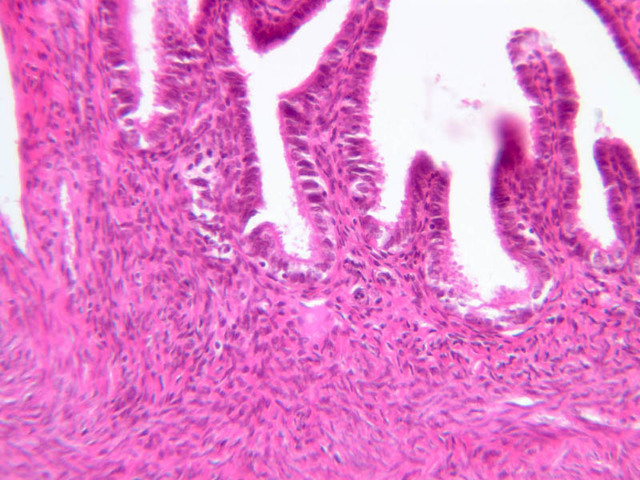

The endometrium of the cervical canal does not slough during the menstrual phase. The glands in this region are relatively large and extensively branched. They are lined by a tall simple columnar epithelium very active in the secretion of mucus. Occasionally these glands become blocked forming Nabothian cysts. The transition of the epithelium of the cervix to that of the vagina is abrupt and is in the region of the external os. At this point, the cervical simple columnar is replaced by the vaginal stratified squamous epithelium (slide B-98 [2.5x-labeled, 10x, 20x, 40x] [2.5x, 10x, 20x, 40x]). This is an area which is commonly inflamed as well as a primary location of cervical cancer.